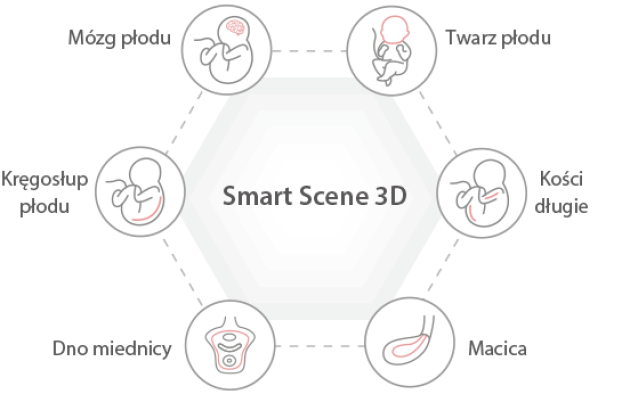

Ultrasonograf Nuewa I9 , zosta? zaprojektowany z my?l? o opiece zdrowotnej kobiet i noworodk├│w. Rozwi?zania zastosowane w Nuewa I9 zosta?y opracowane w oparciu o dog??bn? analiz? r├│?norodnych potrzeb klinicznych, aby zapewni? dok?adn? i szybk? diagnostyk?, a tak?e wyj?tkow? wydajno?? i niezwyk?? wygod? u?ytkowania.